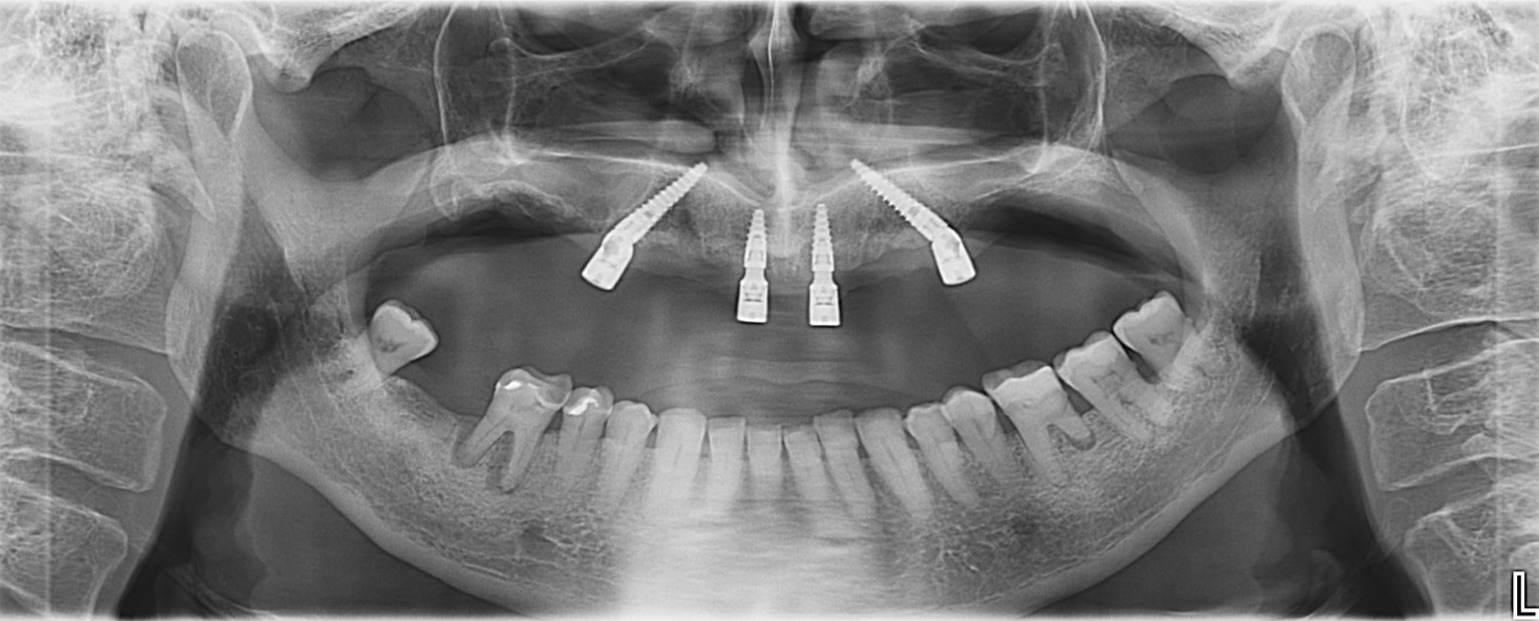

Z minimalno invazivnim ALL ON 4 // ALL ON 6 postopkom vam bomo omogočili fiksne zobe na implantatih - popolno sanacijo zobovja z 4 zobnimi vsadki; dva ki se postavita ravno in dva pod kotom. Tako se preprečijo nekatere anatomske strukture in nadomestilo kosti. Po namestitvi vsadkov sledi priprava začasnega fiksnega mostu na zobne vsadke, ki se lahko izvede že v roku enega dneva po vsaditvi implantatov. Po 6 mesecih se pripravi dokončni fiksni most.

Revolucionarni zobni implantati dolžine tudi do 55 mm odpravljajo potrebo po presaditvi kosti ali dvigom sinusa, saj se vgrajujejo neposredno v jagodične kosti v katerih je dovolj opore za implantate. Ti implantati predstavljaju resnično najboljšo alternativo dolgotrajnemu procesu nadomeščanja (augmentacija) kosti, ki je bila včasih edina rešitev za paciente z hudo resorpcijo čeljustne kosti.

V primeru izjemnega pomanjkanja kosti, ko standardni posegi All on 4 niso mogoči, pa opravljamo rehabilitacijo s sistemi All on 4, ki vključujejo najnovejše subperiostalne, Zygoma ali pterygoidne implantate. Paciente oskrbimo z zobmi že v enem dnevu. V zahtevnejši primerih opravljamo kirurško sedacijo, čas celjenja po operaciji pa je hiter.